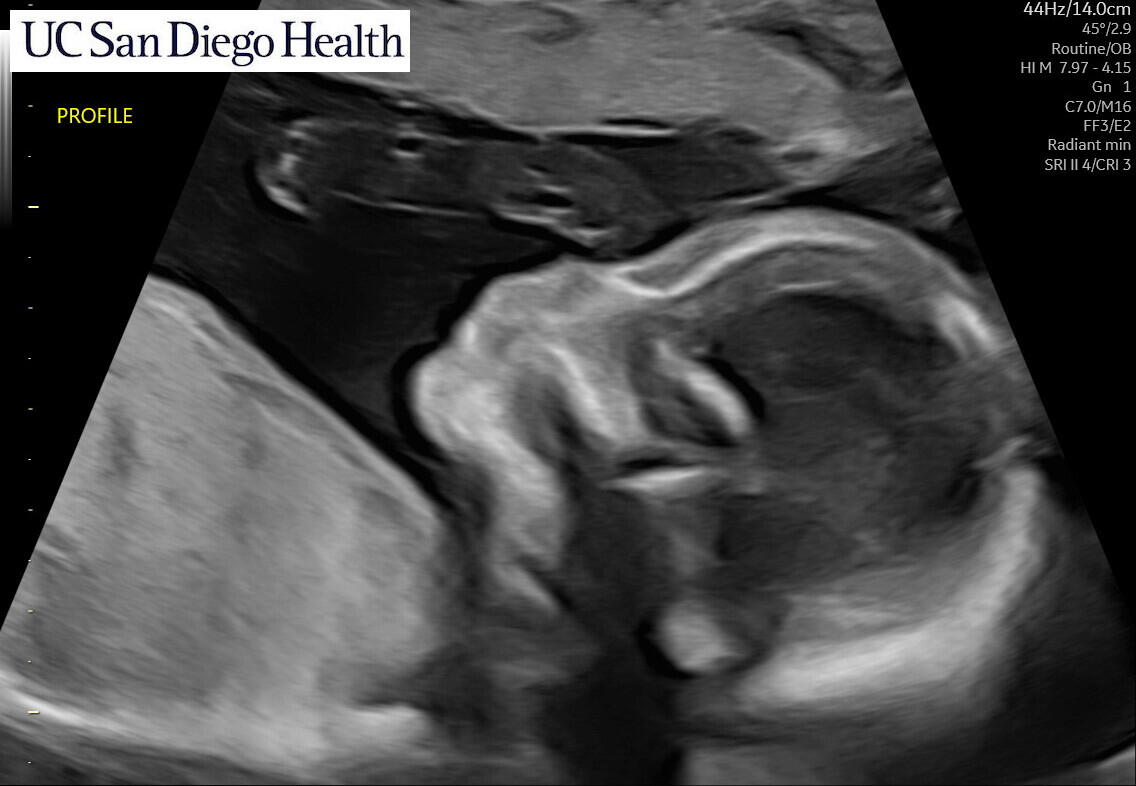

Coming March 2025!

We’re thrilled to be welcoming our baby boy in late March 2025! We’re planning a baby shower in January, we'll see you there!